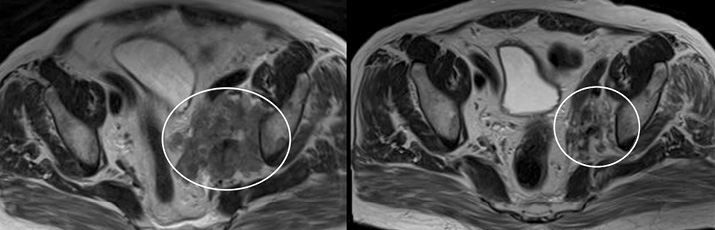

На рис. 9 отражены наиболее наглядные и клинически значимые изменения опухолевого процесса.

Рис. 8. Динамика опухолевого процесса в парагастральных лимфатических узлах.

Чашечно-лоханочная система обеих почек не расширена. Единичные простые кисты в почках до 6 мм. Уменьшились абдоминальные лимфоузлы: парааортальный – до 16 мм в диаметре (ранее 31×25 мм). Уменьшение размеров конгломерата парагастральных лимфоузлов вдоль малой кривизны желудка до 41×21 мм (срез 321, ранее 53×52 мм), который инфильтрует паренхиму поджелудочной железы и подрастает к общей печеночной и селезеночной артериям, селезеночной вене (рис. 8). Уменьшились внеорганные узлы в клетчатке апоневроза, желудочно-ободочной связке, паранефральной клетчатке слева – 8 мм (срез 421, ранее 22 мм).

Рис. 9. Отмечается выраженное уменьшение в размерах опухолево-измененных подвздошных лимфоузлов.